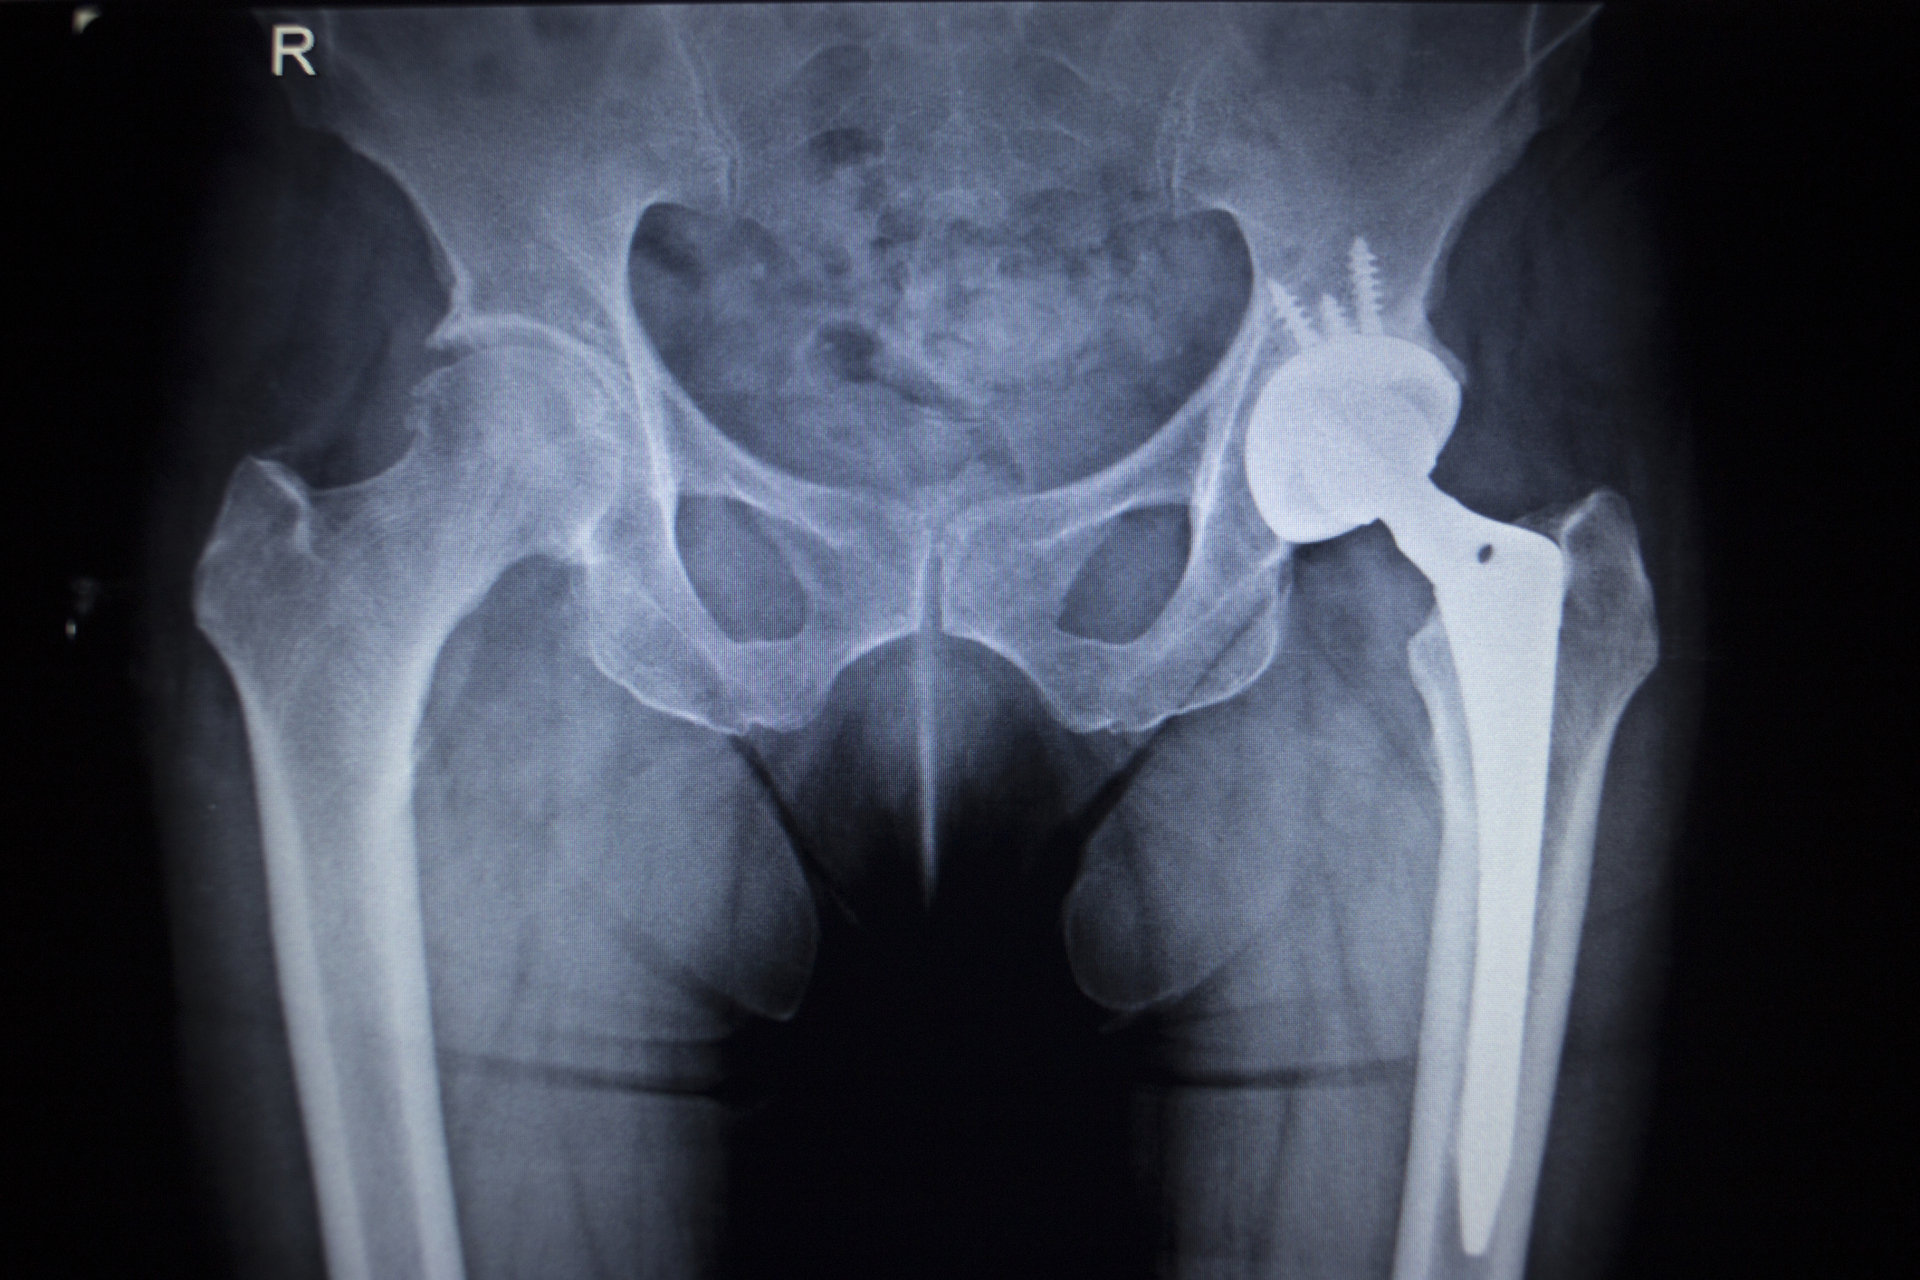

AM is eyed for its abilities to create patient-specific implants. Custom textures increase bone integration, and distinct load-bearing structures can maximize impact-induced bone growth. Often constructed out of "biologically inert" metals like titanium alloys, additive orthopedics have been a driver for the metal AM industry over the past decade.

SmarTech's proprietary market models for additive orthopedics are adapted to growing opportunities in serial manufacturing. Revenue for printers and hardware are expressed in terms of unit sales and installations, and segmented by print technology. It also provides production volumes and forecasts for knee, hip, spine, cranial and facial, and extremities orthopedics.